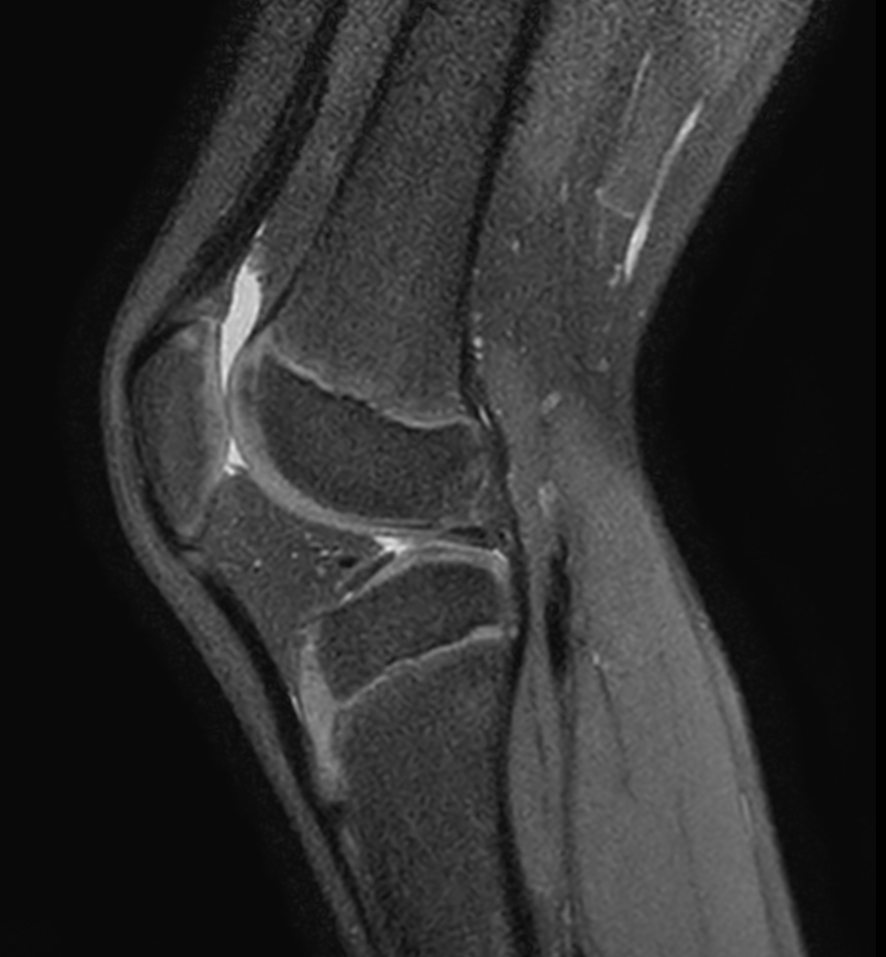

Sagittal PDw SPAIR